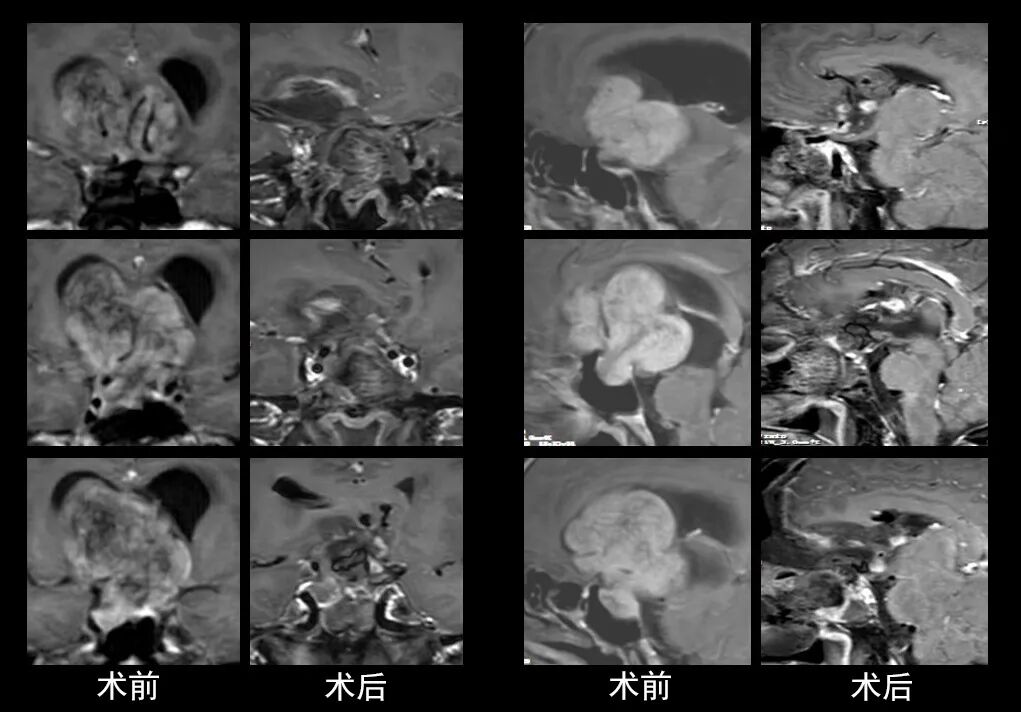

本研究中采用联合手术策略的代表性病例展示:

case 3

case 4